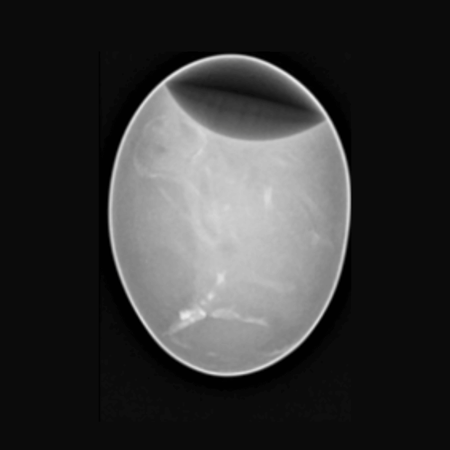

Chicken Egg. Image Credit: Scintica Instrumentation Inc

Chicken X-Ray. Image Credit: Scintica Instrumentation Inc